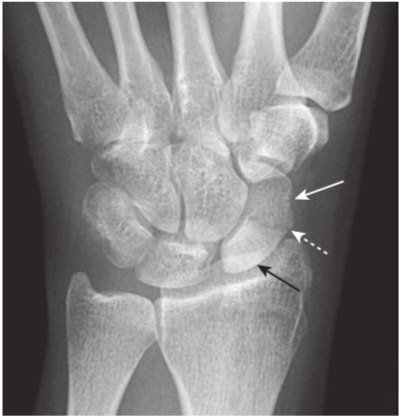

Avascular necrosis of the proximal pole of the scaphoid.

A close-up frontal view of the wrist demonstrates that the proximal pole of the scaphoid (black arrow)is denser than the distal pole (solid white arrow). There is a fracture through the waist of the scaphoid (dotted white arrow). Because of the peculiar blood supply of the scaphoid (from distal to proximal), fractures through the wrist may interrupt the proximal blood supply while the remainder of the bones of the wrist, having normal blood supply, become demineralized. This makes the proximal pole of the scaphoid appear denser relative to the other bones of the wrist.